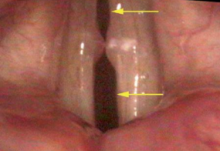

In a pure science mode, I could technically view hoarseness as an impairment of the signal-to-noise ratio of the human voice, yet a more descriptive definition might be more helpful in the clinic. Consequently, I think of hoarseness as an unwanted leak of air though the vocal cords or the irregular leak of air through the vocal cords. This is an often neglected, but incredibly helpful definition.

An air leak in the vocal cords, specifically a split gap.Again, there are only two ways to be hoarse:

1. Air is leaking when you don’t want it to leak.

2. The vocal cords are vibrating irregularly.

That is it. That is the essence and foundation of my entire book. In every patient who complains of hoarseness, we will find one of these two problems: air leak or irregular vibration or some combination of both. Fortunately, it is possible to see air leaking or vocal cords vibrating irregularly, at least with the technology available today.